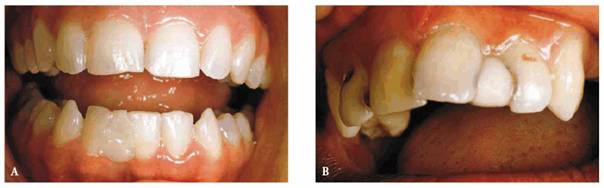

One of the most challenging tasks of modern restorative dentistry is resolving

the dilemma of spaces between anterior teeth. The presence of a diastema can be

a problem because the esthetic value of anterior spacing varies between

cultures, and the best treatment options are often rejected. To some, an

anterior diastema is desirable, whereas others attempt to hide it with habits

such as lip or tongue posturing.6 Some patients have even resorted

to daily applications of wax or cotton to disguise a diastema (Figures 23-1A

and B).

Figure 23-1A and B: Some patients resort to daily applications of materials such as wax (#25) or cotton (#10) to disguise a diastema.